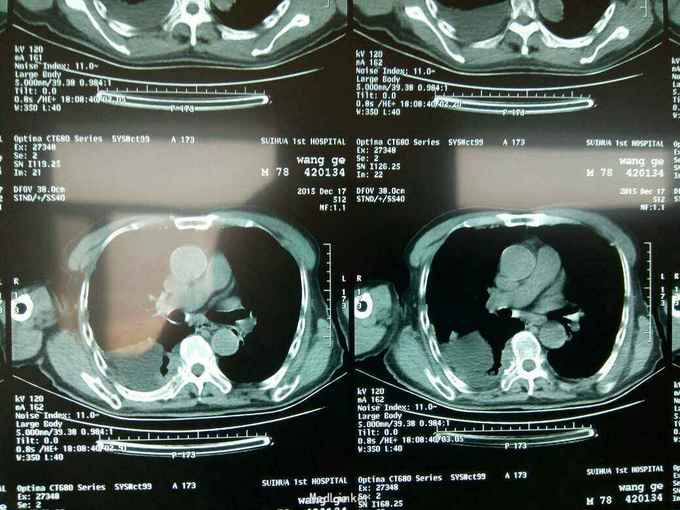

根据病史查体诊断:腰间盘突出症待确诊。应用消肿营养神经镇痛治疗。一天。查核磁共振示:腰椎多节段间盘突出伴椎管狭窄。第二腰椎骨破坏侵及椎板。部分突入椎管,脊髓受压。诊断:腰间盘突出伴椎管狭窄。第二腰椎转移癌,脊髓受压。经与家属沟通,查双肺CT:双肺下叶炎症。肺部纤维化。可见肿瘤阴影。肋骨及胸膜受累。胸椎部分骨破坏。最终诊断:双肺癌,胸椎,腰椎骨转移,脊髓受压。多节段腰椎间盘突出。病人至肿瘤科治疗。